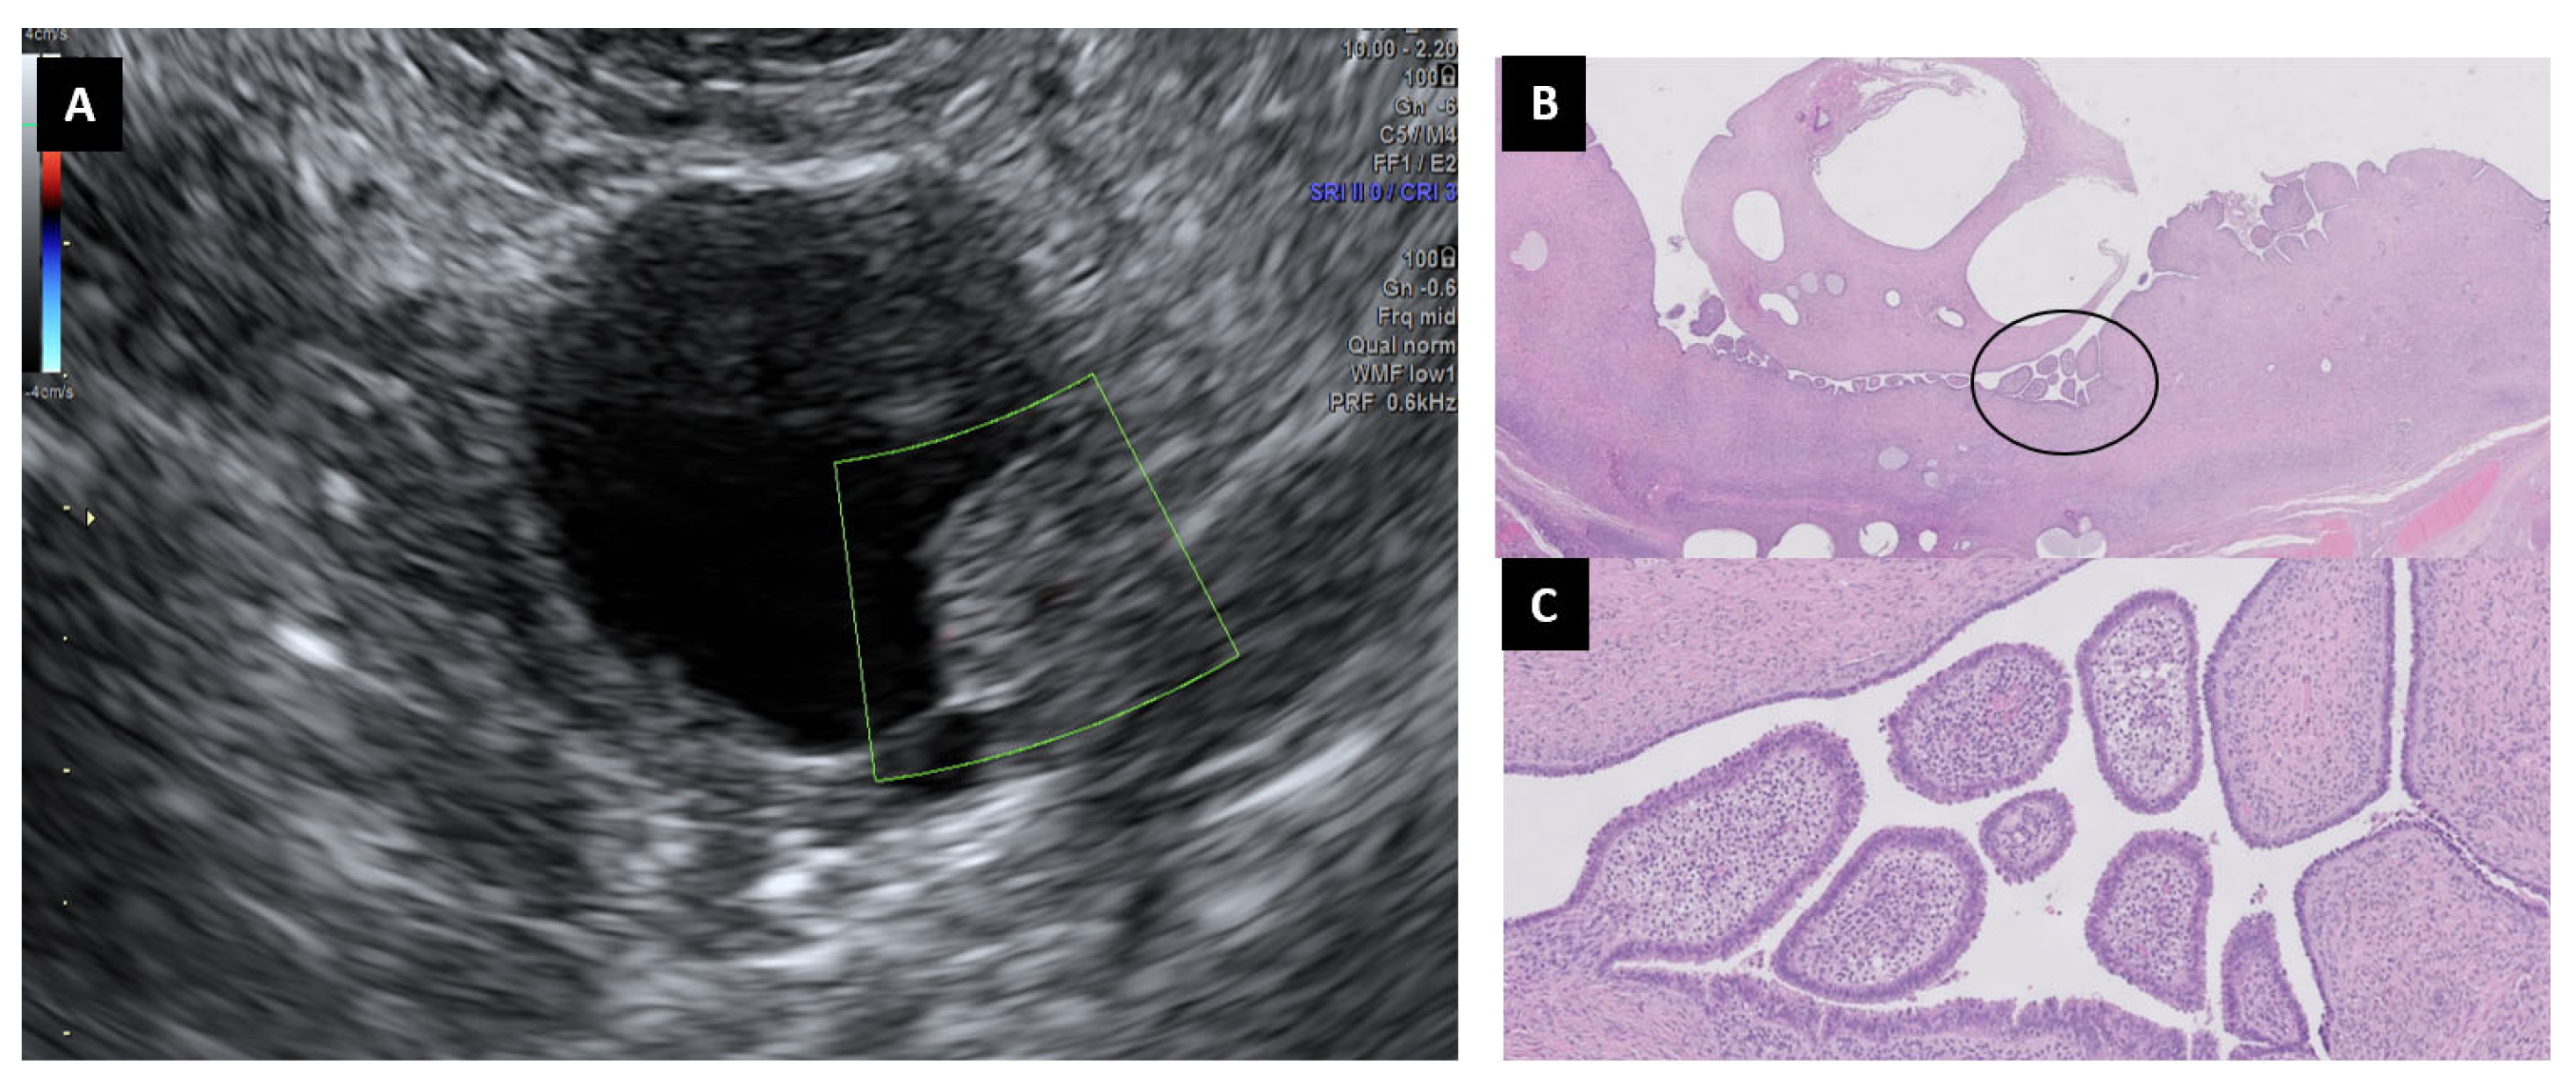

6.2. Cystoadenofibromas

6.3. Mature Cystic Teratomas